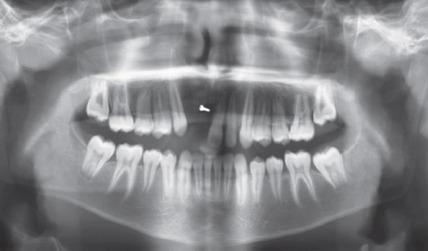

Tooth loss due to trauma often triggers residual alveolar resorption to a greater degree in the sagittal direction leading to atrophy. However, in a pediatric patient, if this defect is left untreated, it can cause further atrophy leading to collapse of the arch. In the maxillary anterior area, this is also of esthetic concern. Hence, it is viable to reconstruct the alveolar defects and restore the alveolar anatomy with superior quality of bone while the patient is still in growing phase to avoid any structural and dental malformation, as well as to provide a more novel treatment like dental implant at a later stage when growth ceases. Modes for successfully augmenting the bone are diverse. Among these, barrier membrane with guided bone regeneration, distraction osteogenesis, and bone block graft is ubiquitous. The current case report deals with the management of horizontal atrophic anterior maxillary region using autologous block bone graft harvested from mandibular symphysis, to augment the alveolar ridge and aid in esthetic and functional restoration of alveolar anatomy by restoring the defect with the bone of superior quality as well as preparing the site for receiving implant prosthesis in future when growth ceases. Bhandary M, Hegde AM, Shetty R, Augmentation of Narrow Anterior Alveolar Ridge Using Autogenous Block Onlay Graft in a Pediatric Patient: A Case Report. Int J Clin Pediatr Dent 2021;14(2):311-314.

因创伤导致的牙齿缺失通常会在矢状方向上更大程度地引发残余牙槽骨吸收,进而导致萎缩。然而,对于儿科患者,如果这种缺损不进行治疗,可能会导致进一步萎缩,进而导致牙弓塌陷。在上颌前部区域,这也涉及美观问题。因此,在患者仍处于生长阶段时,重建牙槽骨缺损并恢复具有优质骨的牙槽骨解剖结构是可行的,以避免任何结构和牙齿畸形,并在生长停止后的后期提供更新颖的治疗方法,如牙种植体。成功增加骨量(骨增量)的方式多种多样。其中,引导骨再生屏障膜、牵张成骨和骨块移植很常见。本病例报告涉及使用从下颌联合处获取的自体块状骨移植来处理上颌前部水平萎缩区域,以增加牙槽嵴,并通过用优质骨修复缺损以及为生长停止后未来接受种植修复体准备位点,来帮助牙槽骨解剖结构的美观和功能恢复。Bhandary M, Hegde AM, Shetty R, 儿科患者使用自体块状贴附移植增加狭窄前牙槽嵴:病例报告。《国际临床儿科牙科学杂志》2021年;14(2):311 - 314。